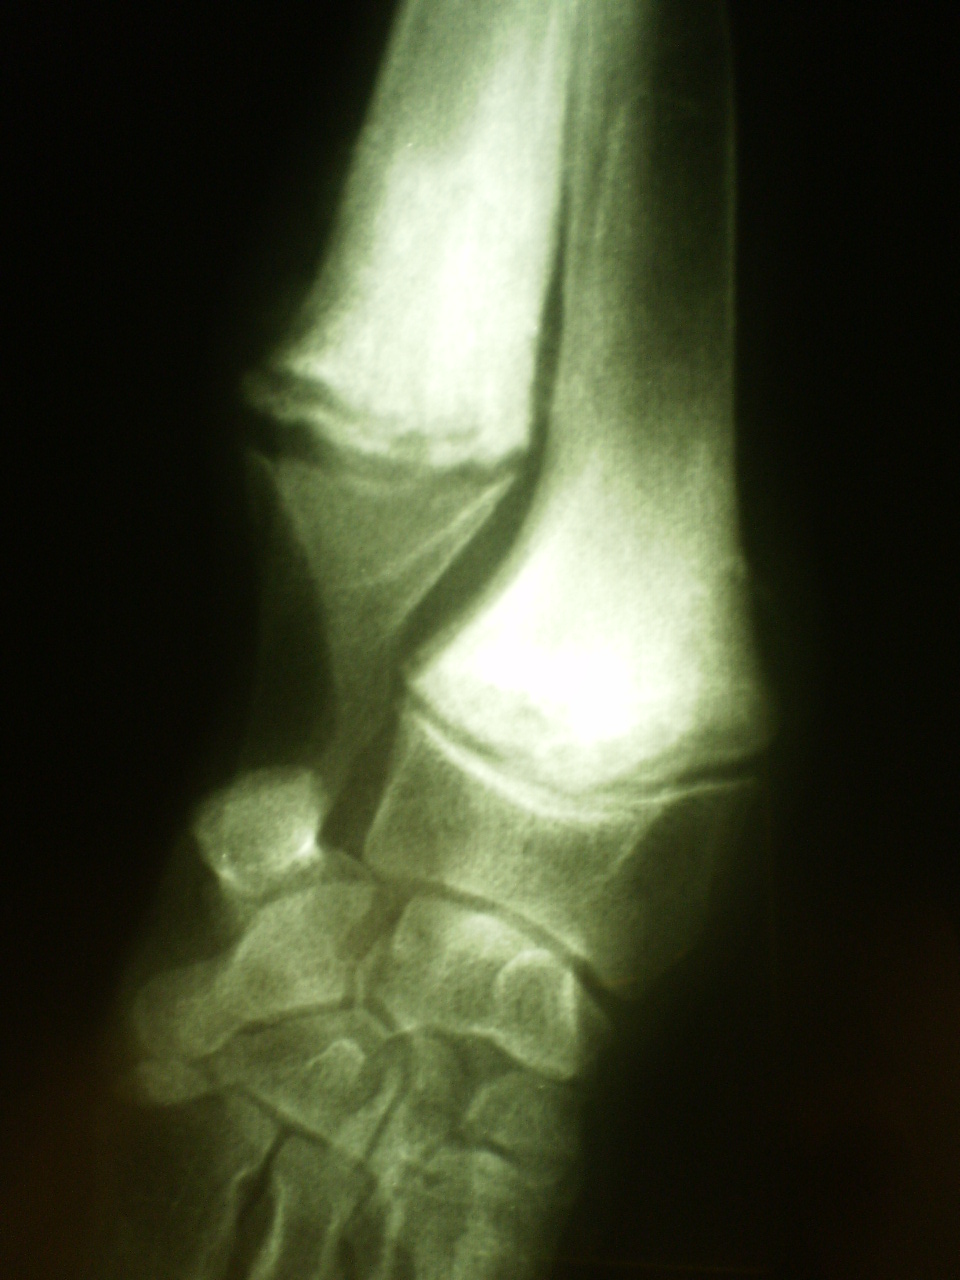

Por ello, la rx simple, es limitada para valorar la estabilidad de la articulacion ,y debemos realizar rx de estres en hiperflexion, hiperextension y bostezos lateral y meial.

En este caso la rx en hiperflexion nos evidencia la inestabilidad dorsal.